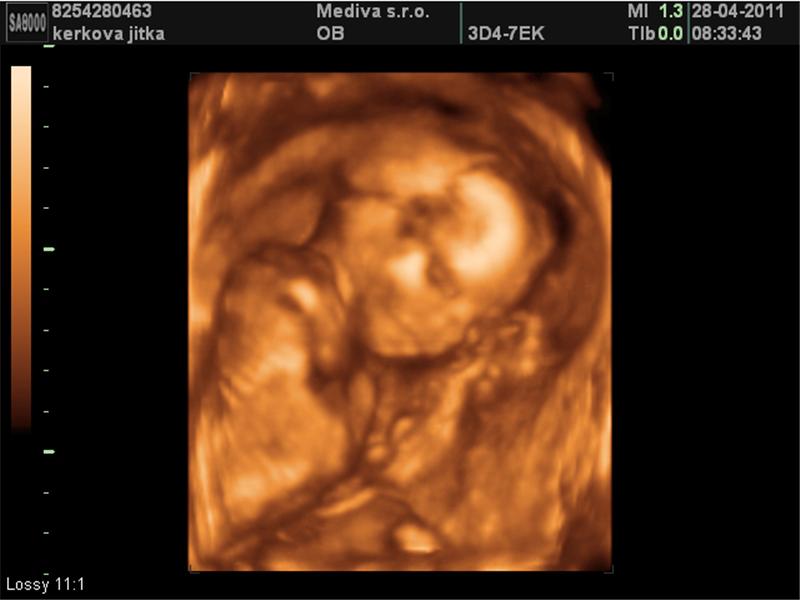

Ultrazvuky

3 fotografií